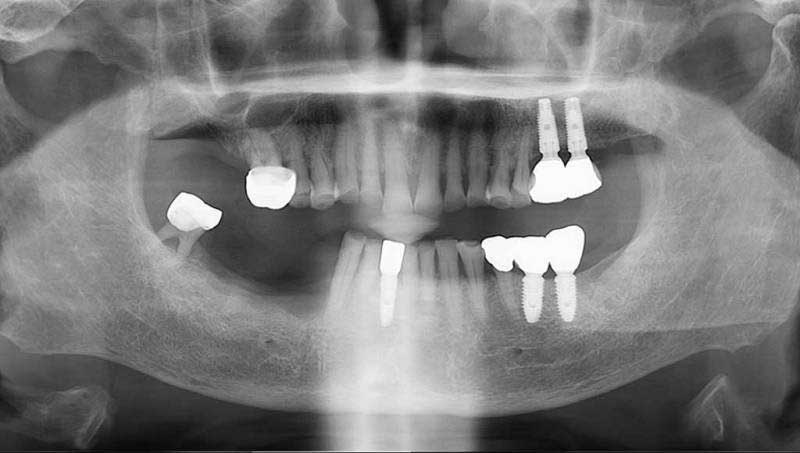

案例2

植牙併發症處理前

植牙併發症處理後